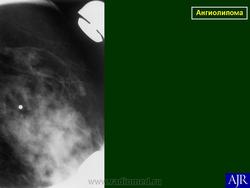

Ангиолипома.